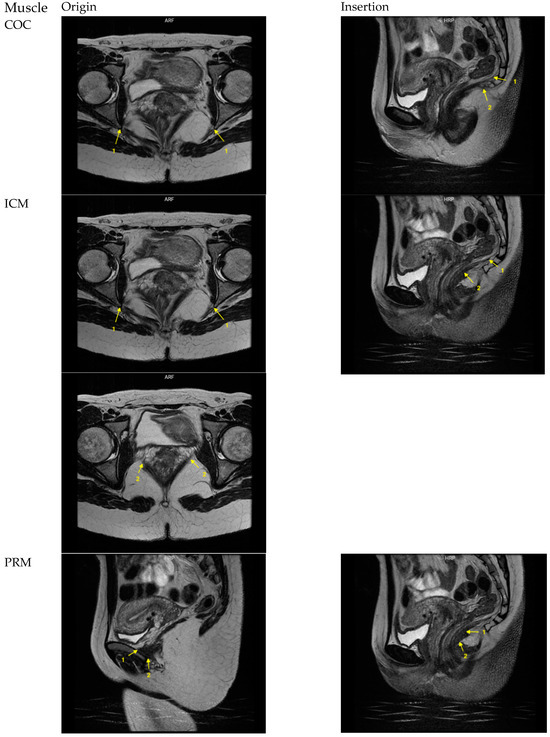

| PVM | 4 points, 2 on each side | see PAM, PVaM, PPM | Coronal | See PAM, PVaM, PPM | Originating from os pubis 1: most cranial and posterior muscle fibers 2: muscle fibers at the most anterior end at the symphysis | see PAM, PVaM, PPM |

| PAM | See PVM | 2 points, 1 on each side | See PVM | Axial | See PVM | Distinct longitudinally directed muscle fibers inserting into the intersphincteric groove between the internal and external anal sphincter Most distal plane in the midline, point placing at 3 and 9 o’clock of the rectum |

| PVaM | See PVM | 4 points, 2 on each side | See PVM | Axial | See PVM | Most distal visible fibers at the vaginal side wall at the level of the mid-urethra 1: most anterior muscle fibers 2: most posterior muscle fibers |

| PPM | See PVM | 1 point in the midline | See PVM | Axial | See PVM | Most distally visible muscle fibers inserting in the perineal body. Point placement anteriorly of the anal canal, one point in the midline |